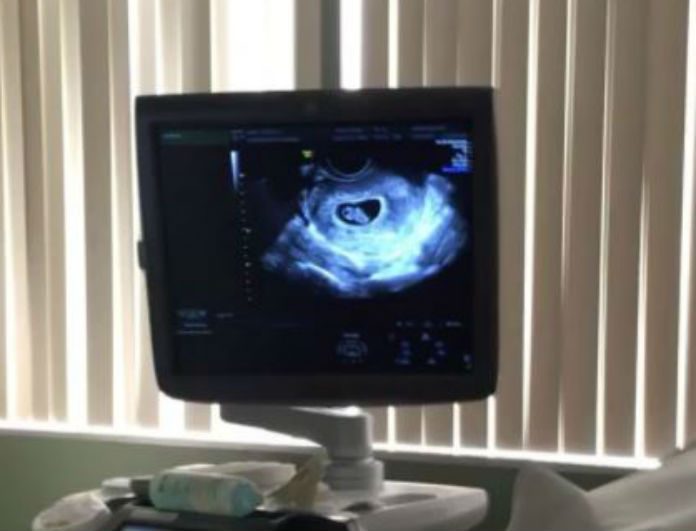

Τόσο ο Neyo όσο και η διάσημη ηθοποιός Crystal Smith, δημοσίευσαν βίντεο από τη στιγμή που βλέπουν στο μόνιτορ του υπερηχογραφήματος το μωράκι τους!

Ο 38χρονος τραγουδιστής σχολίασε κάτω από το βίντεο, «Ορκίζεται ότι είναι κορίτσι…», ενώ η σύζυγός του που δημοσίευσε το ίδιο βίντεο στον δικό της προσωπικό λογαριασμό στα social media έγραψε, «Είναι πραγματικά απίστευτη η εμπειρία και η ευλογία να κυοφορείς ένα παιδί. Το μικρό μας βατομουράκι έχει χέρια και πόδια τώρα πια ενώ η καρδιά του χτυπά σαν τρελή. 8η εβδομάδα εγκυμοσύνης. Ειλικρινά θα είμαι χαρούμενη είτε είναι αγόρι, είτε κορίτσι θέλω να είναι υγιές… αλλά η μαμά μπορεί να ελπίζει για ένα κορίτσι…».

Δείτε το βίντεο: